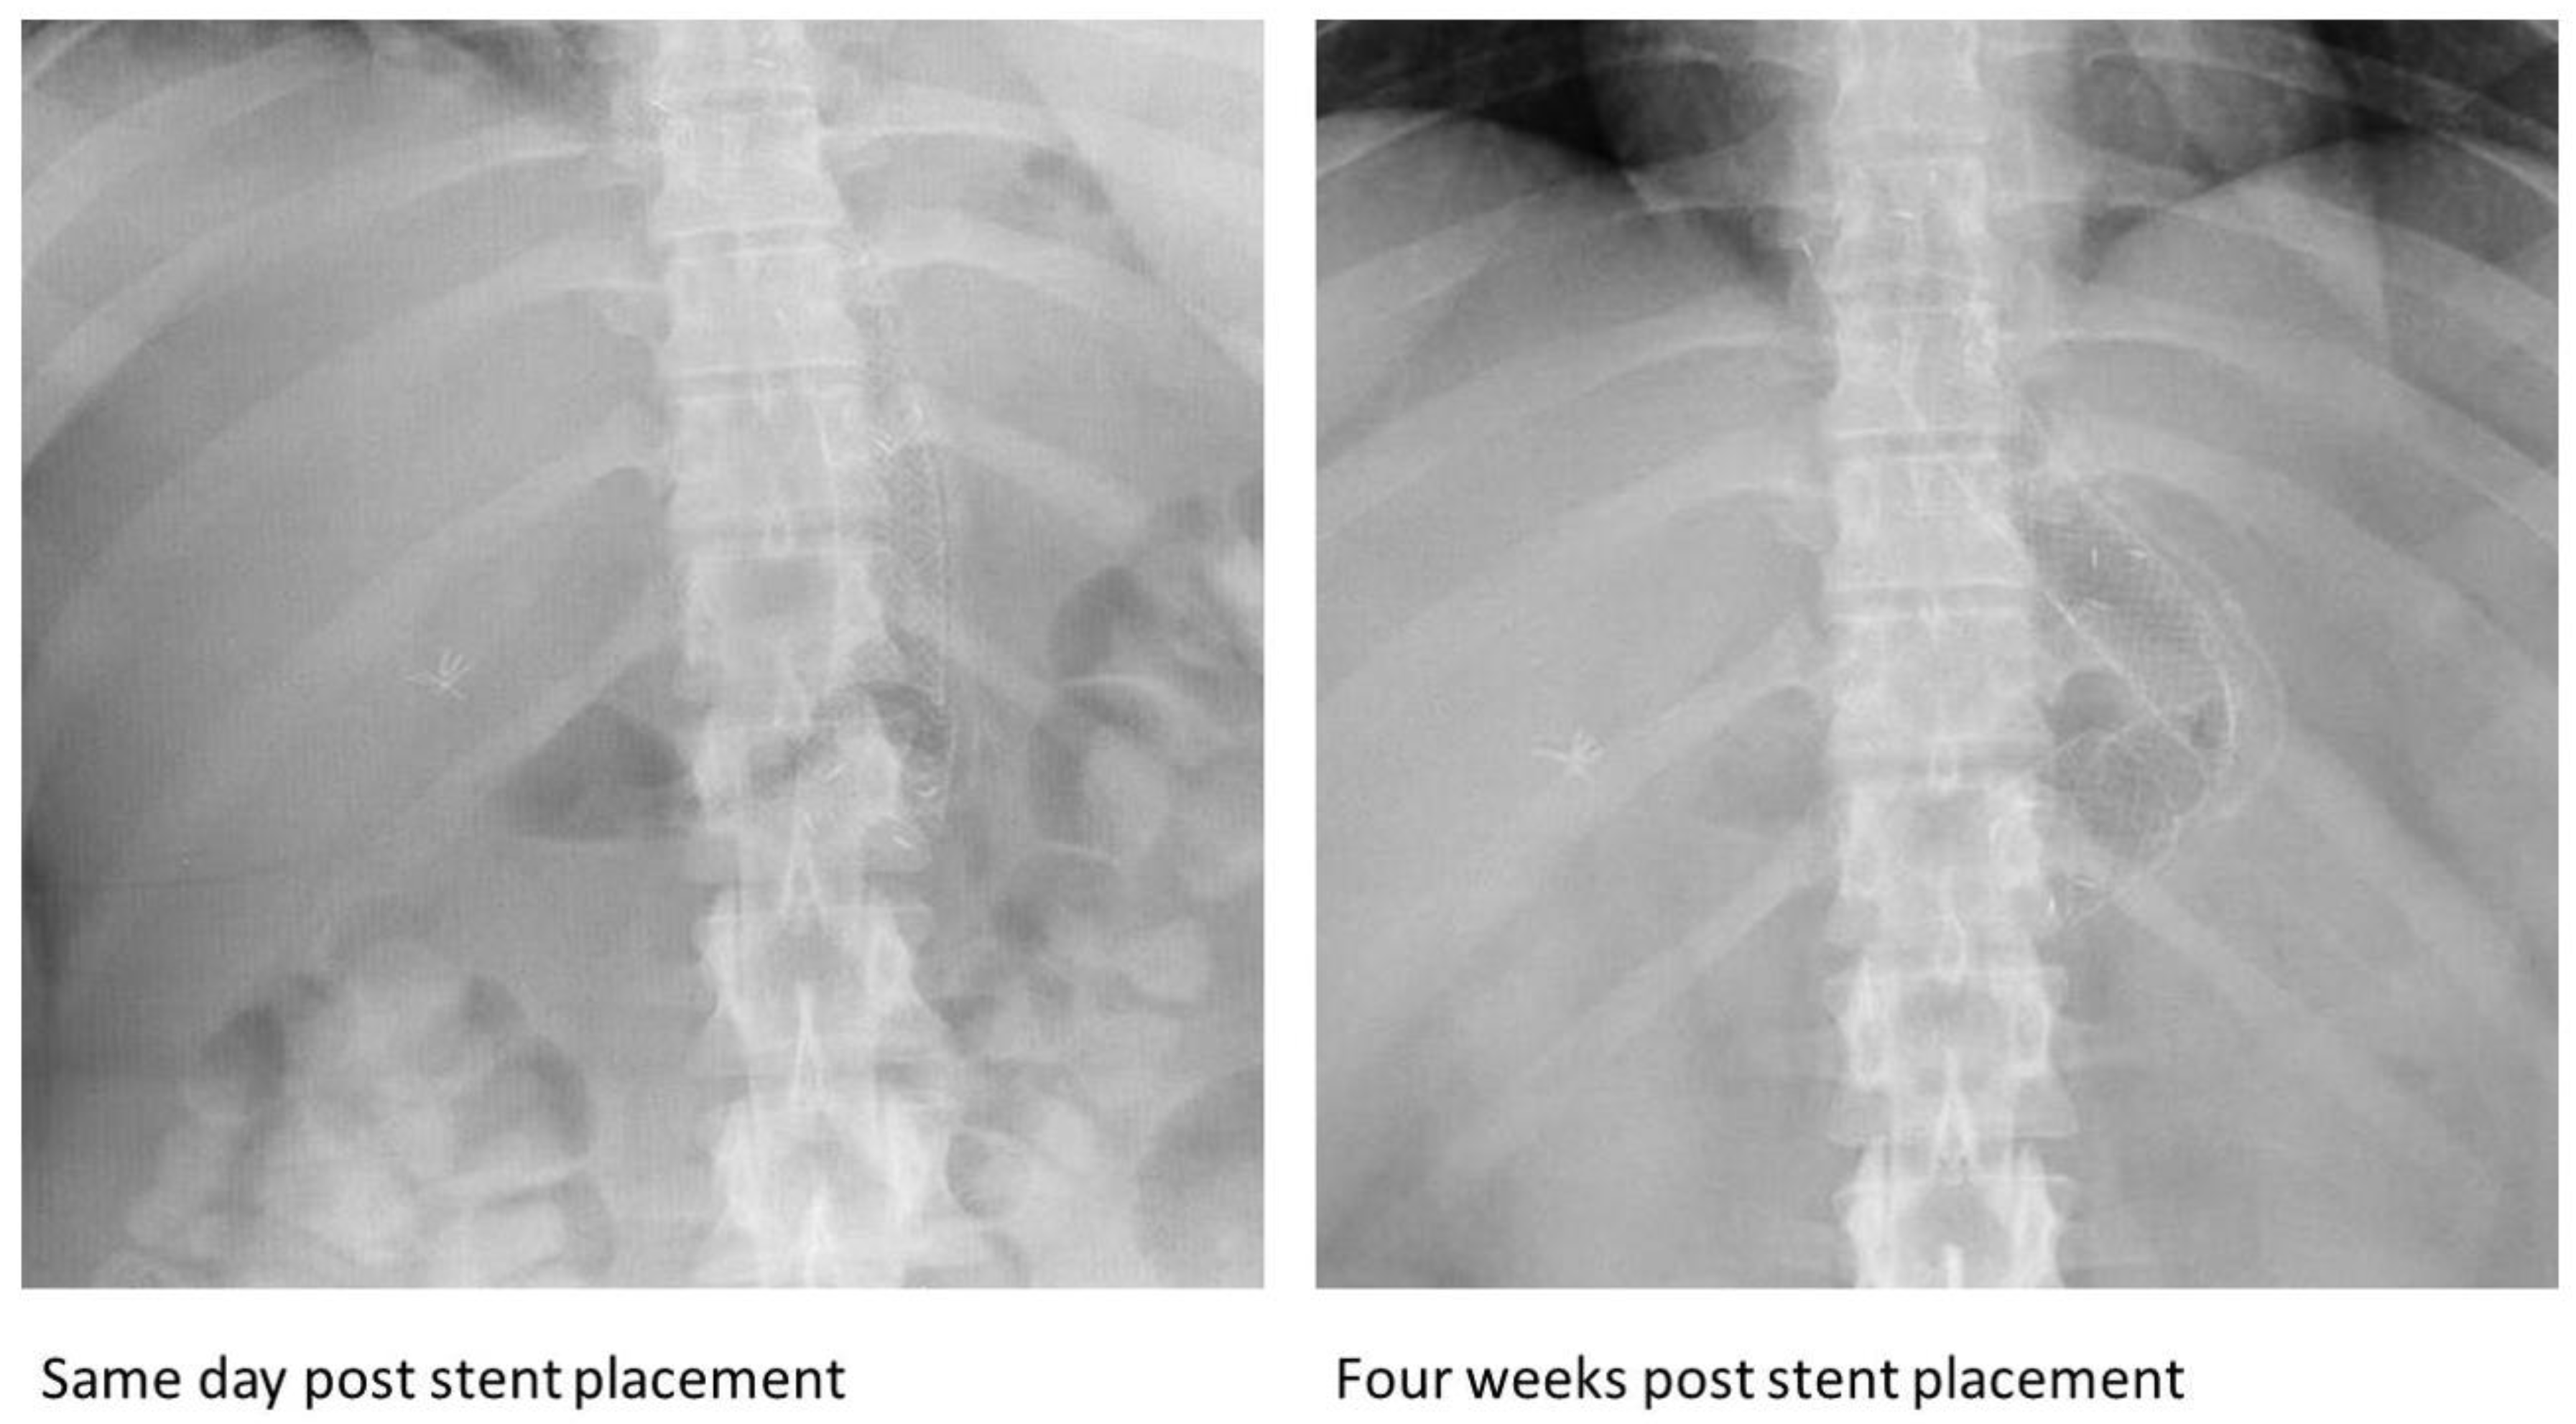

| Some cases were diagnosed by imaging [8,9,11,12,13,16,20,24,32] Most were diagnosed during or after endoscopic removal | All the SEMS fractured in vivo and were noted during or after endoscopic removal. | ||